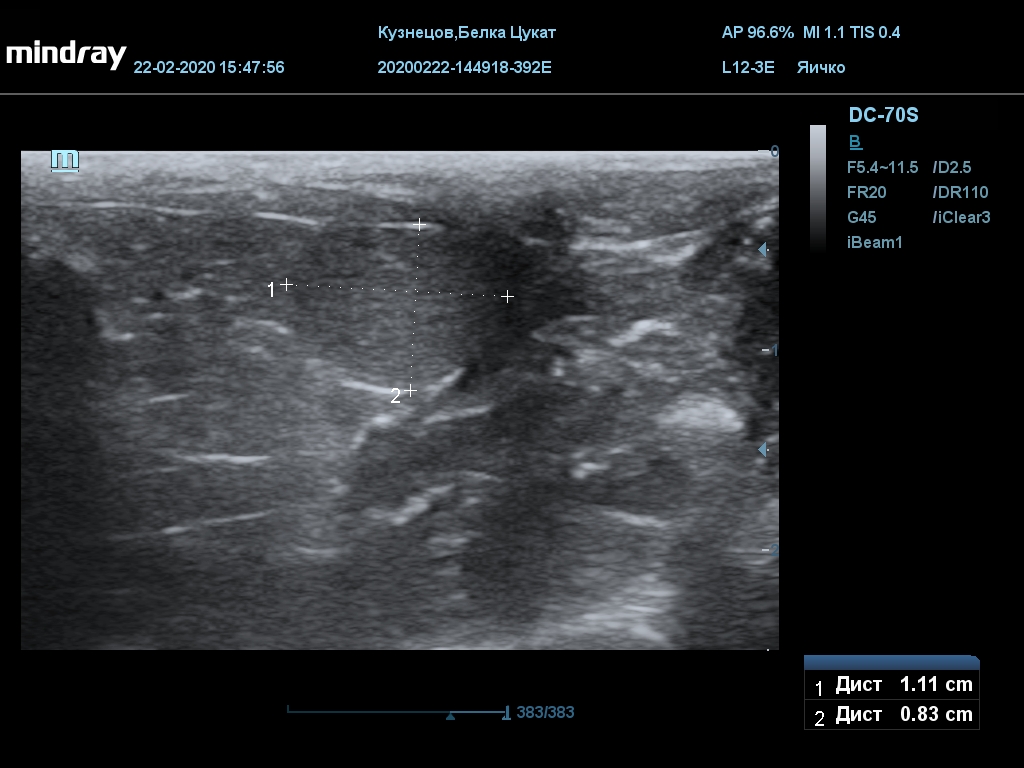

УЗИ

(почки, мочевой пузырь и, предположительно, простата)

Обращаю внимание, что делала УЗИ и писала заключение узист, которая специализируется на кошках и собаках, поэтому она сделала узи и описала, как смогла, но тонкостей грызунячьей анатомии она не знает.

Приложил только фото, есть ещё пара видео, но не знаю, как тут выложить, и надо ли.

Мочевой пузырь объём 12,1 х 7,6 х 11 мм. Стенка не утолщена, 0,5 мм, содержимое не однородное, до половины объёма гипоэхогенная мелкодисперсная взвесь. Макс. размер включений 0,8 мм. Теней нет.

Каудальнее мочевого пузыря визуализируется округлая структура размером 11,1 х 8,3 мм с ровными контурами гипоэхогенная однородная, с признаками васкуляризации.

Почка левая ровная, размер 12 х 7,6 х 8,2 мм. Контур ровный чёткий. КМД отсутствует, лоханка расширена незначительно, объёмных включений не выявлено.

Почка правая ровная, контур чёткий, размер 13,5 х 8,7 х 9,3 мм. Капсула визуализируется. КМД отсутствует, лоханка не расширена. Объёмные образования не выявлены.

Заключение: УЗпризнаки уролитиаза, объёмная структура каудальнее мочевого пузыря. Признаки расширения левой лоханки.

УЗИ

(почки, мочевой пузырь и, предположительно, простата)

Обращаю внимание, что делала УЗИ и писала заключение узист, которая специализируется на кошках и собаках, поэтому она сделала узи и описала, как смогла, но тонкостей грызунячьей анатомии она не знает.

Приложил только фото, есть ещё пара видео, но не знаю, как тут выложить, и надо ли.

Мочевой пузырь объём 12,1 х 7,6 х 11 мм. Стенка не утолщена, 0,5 мм, содержимое не однородное, до половины объёма гипоэхогенная мелкодисперсная взвесь. Макс. размер включений 0,8 мм. Теней нет.

Каудальнее мочевого пузыря визуализируется округлая структура размером 11,1 х 8,3 мм с ровными контурами гипоэхогенная однородная, с признаками васкуляризации.

Почка левая ровная, размер 12 х 7,6 х 8,2 мм. Контур ровный чёткий. КМД отсутствует, лоханка расширена незначительно, объёмных включений не выявлено.

Почка правая ровная, контур чёткий, размер 13,5 х 8,7 х 9,3 мм. Капсула визуализируется. КМД отсутствует, лоханка не расширена. Объёмные образования не выявлены.

Заключение: УЗпризнаки уролитиаза, объёмная структура каудальнее мочевого пузыря. Признаки расширения левой лоханки.